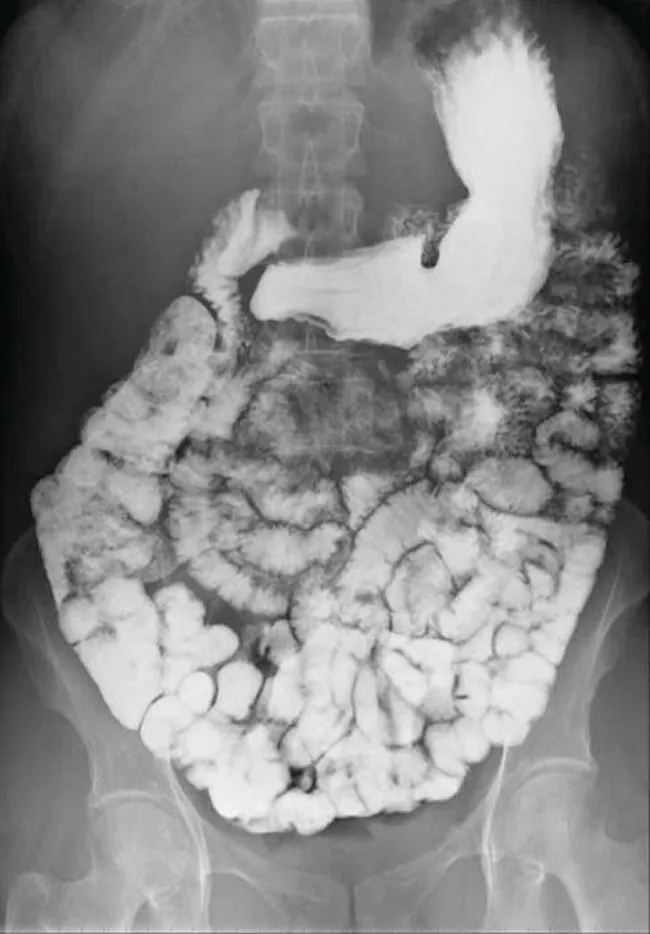

Various types of medical imaging techniques are used to aid diagnoses of illnesses in a noninvasive manner. One such technique utilizes the ingestion of a barium compound before taking an X-ray image. A suspension of barium sulfate, a chalky powder, is ingested by the patient. Since the Ksp of barium sulfate is 1.1 ×× 10–10, very little of it dissolves as it coats the lining of the patient’s intestinal tract. Barium-coated areas of the digestive tract then appear on an X-ray as white, allowing for greater visual detail than a traditional X-ray (Figure 15.4).

This figure contains one image. A black and white abdominal x-ray image is shown in which the intestinal tract of a person is clearly visible in white.

Figure 15.4 The suspension of barium sulfate coats the intestinal tract, which allows for greater visual detail than a traditional X-ray. (credit modification of work by “glitzy queen00”/Wikimedia Commons)

Further diagnostic testing can be done using barium sulfate and fluoroscopy. In fluoroscopy, a continuous X-ray is passed through the body so the doctor can monitor, on a TV or computer screen, the barium sulfate’s movement as it passes through the digestive tract. Medical imaging using barium sulfate can be used to diagnose acid reflux disease, Crohn’s disease, and ulcers in addition to other conditions.